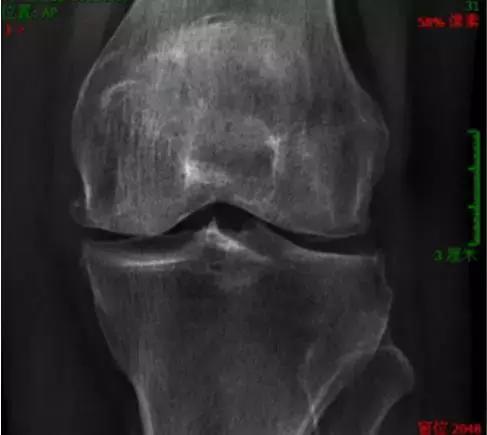

6 假性痛风

男性患者多,好发于膝关节。发作时肿胀疼痛、皮温高、功能受限。X线片表现半月板、关节软骨面钙化。

什么是膝骨关节炎呢?

骨关节炎又称退行性关节病、增生性关节炎等,一般认为是一种以软骨变性、破坏及骨质增生为特点的关节病,但实际上其也存在关节炎症并可以累及整个关节。膝关节是骨关节炎最常见的发病部位之一。

上下楼关节疼痛警惕骨性关节炎

骨性关节炎是一种退行性病变,可分为原发性和继发性两大类,多见于中老年人,易发在负重较大的膝、髋关节。其病因可能与年龄、肥胖、职业性过度使用等因素有关。60岁以上老年人过半都患有骨关节炎。最常见的症状是早期关节的疼痛。这种疼痛最明显的表现为上下楼梯,特别是下楼梯时膝关节的疼痛。此外比较明显的症状还有晨起时关节僵硬;长期保持一个姿势后,变换姿势时关节活动受限等。